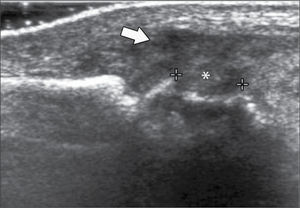

En operadores entrenados (8) permite una buena evaluación de los tendones del manguito rotador, incluso comparable con la RM (9) en busca de tendinosis, tendinopatía cálcica y roturas (figuras 2-4).

En el tendón de la porción larga del biceps es útil para estudio de tenosinovitis o luxación. En articulación acromioclavicular podemos encontrar compromiso degenerativo o inflamatorio, derrame, quistes periarticulares o signos indirectos de disyunción. Se visualiza el receso articular glenohumeral posterior en búsqueda de derrame y también los planos musculares periarticulares. La bursitis subacromiodeltoidea se manifiesta como engrosamiento y/o líquido en la bursa (figura 5). La evaluación dinámica permite observar fenómenos de pinzamiento por el ligamento coracoacromial y también pinzamiento subacromial a la bursa o los tendones.